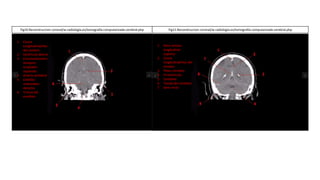

IDENTIFICANDO ESTRUCTURAS EN UNA

TOMOGRAFIA AXIAL COMPUTARIZADA

(RECONSTRUCCION CORONAL)

1. Circunvoluciones

frontales

2. Musculo recto externo

3. Cornete nasal

4. Seno Maxilar

1. Circunvoluciones frontales

2. Arco cigomático

3. Mandíbula

4. Cornete nasal

5. Arco alveolar

6. Seno maxilar derecho

Fig4. Reconstrucción coronal/w-radiología.es/tomografía-computarizada-cerebral.php Fig5. Reconstrucción coronal/w-radiología.es/tomografía-computarizada-cerebral.php

SECUENCIAS ANTERO-POSTERIORES